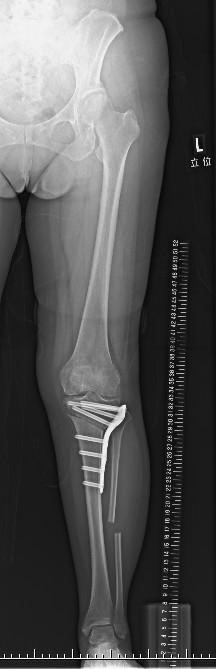

骨切り術後のレントゲン写真

関節の部分はそのまま残すので、膝の曲げ伸ばしの状態は手術前と変わりません。たとえば、術前にしゃがむことができている方であれば、術後もしゃがむことができます。

骨切り術は膝関節を切らない術式であるため、ご自身の膝関節を温存できることが特徴です。術後、O脚の方はX脚気味になります。